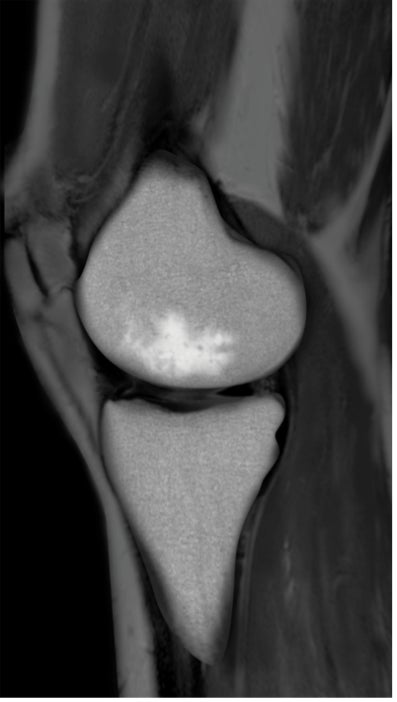

BML(Bone marrow lesion、骨髄異常陰影)はMRIで発見することのできる骨髄内の異常のことを言い、軟骨の下の骨の微小骨折による骨髄内の炎症または浮腫(水分が骨に溜まった状態)、壊死(骨が死んでしまった状態)をあらわすとされています。

BMLは痛みと強い関係があることが示されていて、標準的な保存治療のヒアルロン酸注射や近年注目されている再生医療のPRP療法でも改善しない関節痛の原因となっている可能性が指摘されています。

BMLが生じた膝関節のMRI画像